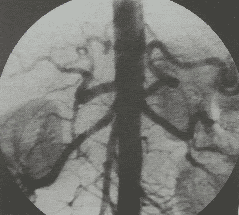

Ống thông được đưa vào động mạch đùi chung bên tổn thương để chụp mạch. Kỹ thuật chụp mạch được sử dụng là chụp mã hoá xoá nền (DSA), giúp cung cấp hình ảnh với độ phân giải cao hơn và xoá bỏ các phần không liên quan đến mạch máu (xương, phần mềm), giúp bộc lộ tổn thương tốt hơn.

Chụp mã hóa xóa nền giúp chụp động mạch đùi